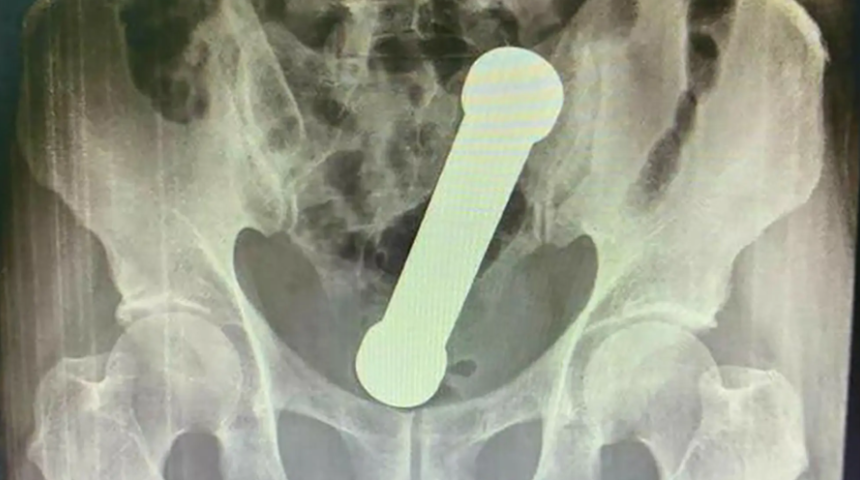

Brezilya’da yaşayan ve ismi açıklanmayan 54 yaşındaki bir adam dayanılmaz karın ve mide ağrıları ile günlerce süren kabızlık semptomlarıyla doktora başvurdu. Manaus kentindeki hastaneye başvuran ve tedavisine başlanan adamın ilk anal muayenesinde her şey normal bir şekildeydi. Ancak doktorlar bölgeyi bir de röntgenle ile taramaya karar verdiklerinde kolon ve rektumun kesiştiği noktada bir dambıl olduğunu fark ettiler.

Dambılın anal delinme veya başka bir ağır yaralanmaya neden olmasını önlemek için hızlı hareket eden doktorlar hastayı acilen ameliyata aldı.

Genel anestezi yöntemiyle ameliyatına başlanan adamın makat bölgesi yırtılmadan ve kanama olmadan başarılı bir şekilde dambıl çıkartıldı. Operasyonun başarılı bir şekilde tamamlanmasıyla birlikte ismi açıklanmayan hasta 3 gün sonra taburcu edildi.